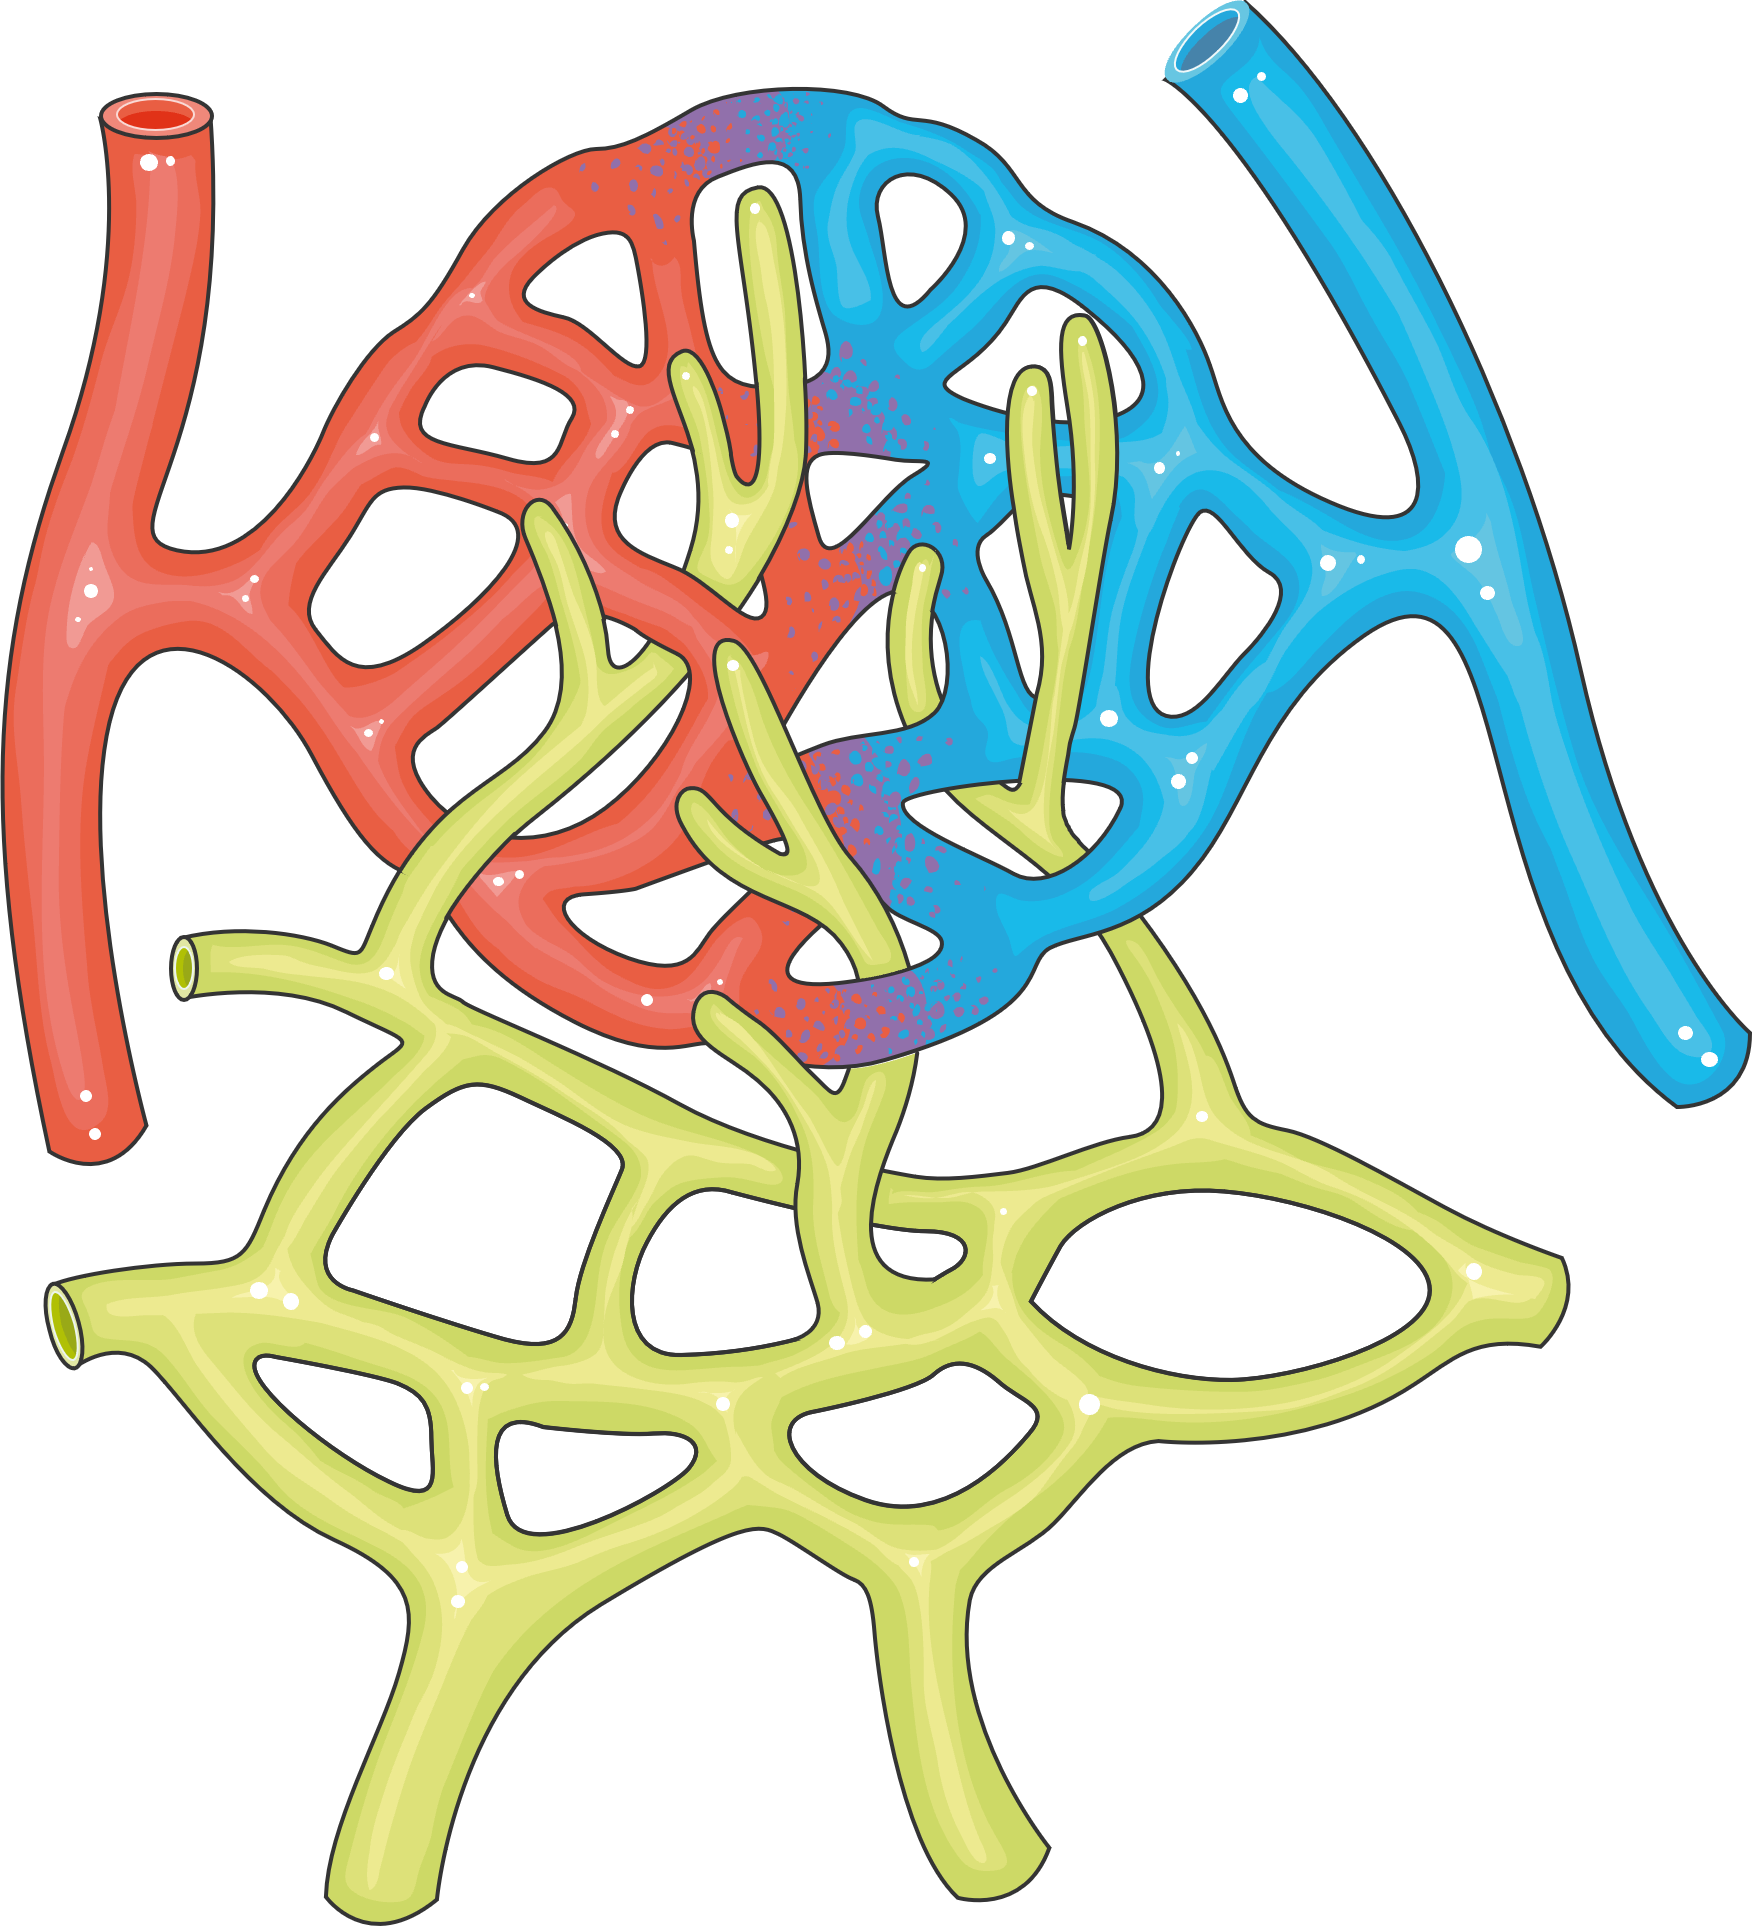

Not in diagnostic criteria but commonly seen on biopsy. Typical pathology includes MPGN-like lesions, mesangiolytic glomerulonephritis, or thrombotic microangiopathy. Electron microscopy shows glomerular microangiopathy with endothelial injury — the same endothelial damage found in nerve vasa nervorum, suggesting generalized endothelial injury is a unifying mechanism.

eGFR below 30 mL/min is an adverse prognostic factor. Can improve with bortezomib-based treatment.